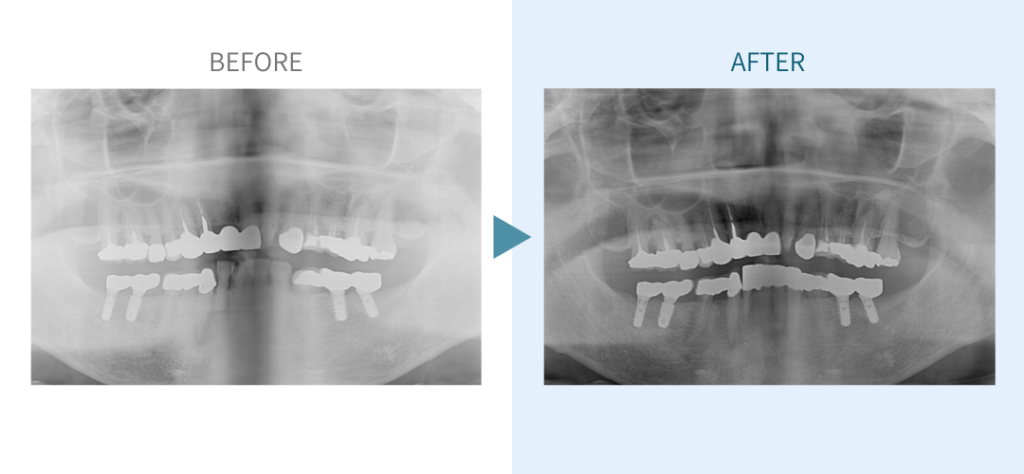

デンタルチームジャパンでは、サイナスリフト(上顎洞底挙上術)や骨造成など、他院で「骨が足りない」と断られた難症例にも対応しています。

こうしたケースは一般的に大学病院以外では難しく、大学で治療を受ける場合は費用が当院の倍以上になることもあります。

私たちは、難症例に関する治療法を学会でも発表しており、その豊富な実績と技術力が評価され、全国から患者様が来院いただいております。

こちらではその一部の症例についてご紹介します。